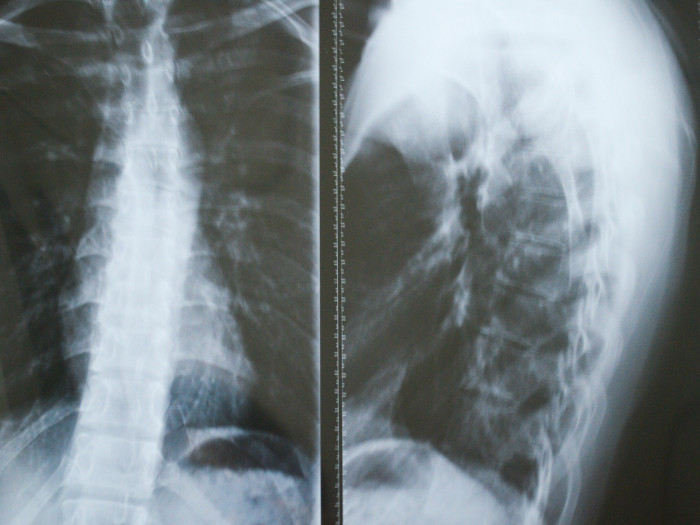

Doctors typically rely on advanced imaging techniques, such as X-rays, MRIs, or CT scans, to monitor bone loss and assess the extent of the disease. A definitive diagnosis is usually confirmed through a bone biopsy, which reveals non-cancerous vascular tissue replacing the bone.